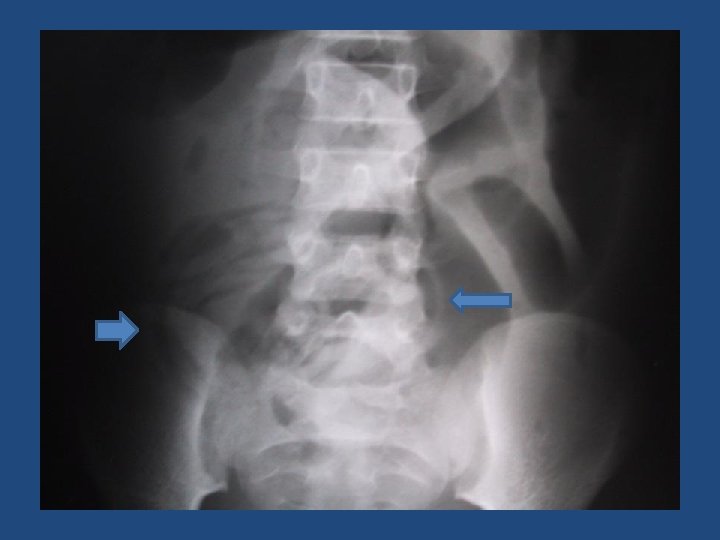

Typhoid – Pneumoperitoneum

Indications for surgery: • Pneumoperitoneum on x-ray (may require left lateral film) • Persistent palpable mass (especially with erythema of abdominal wall) • Diffuse peritonitis or positive peritoneal tap • Persistent sepsis/failure to improve on medical therapy • Suspicious of abdominal catastrophe but negative x-rays? Do frequent examinations (by the same or equally experienced examiner) and x-rays (q. 6 h at first) until improvement or perforation is evident.